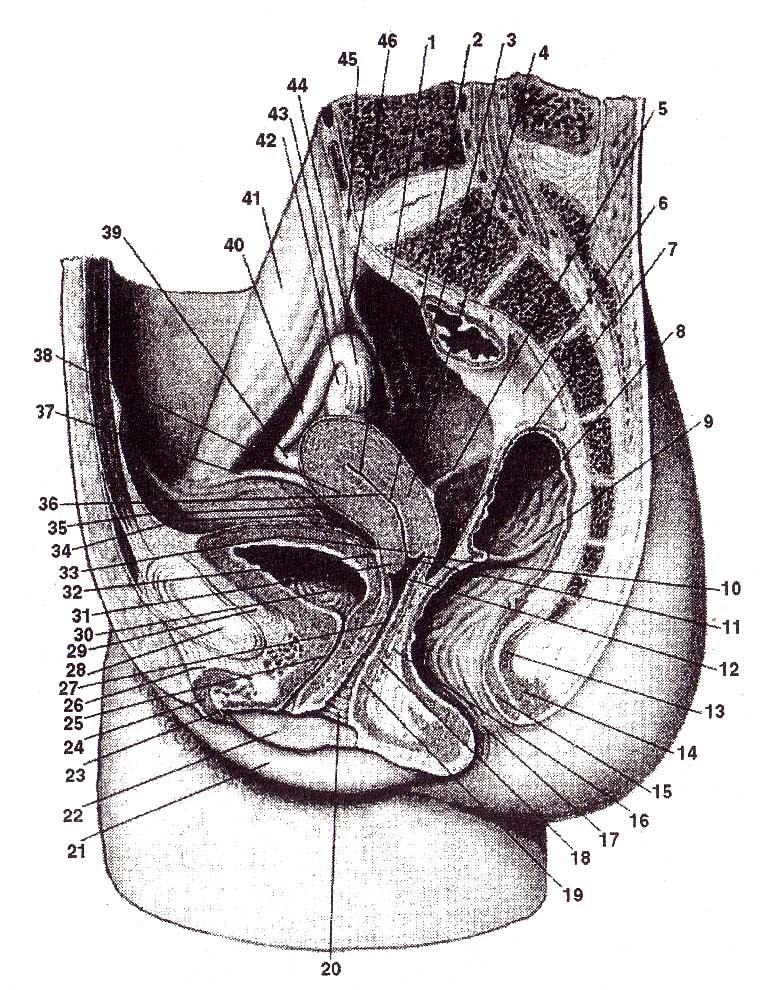

Анатомия малого таза: детальные схемы и изображения